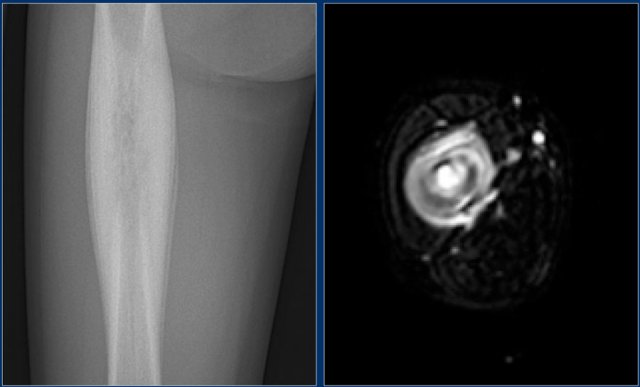

Here another case of osteomyelitis.

There is cortical thickening, sclerosis and a layered periosteal reaction.

Axial T2-weighted fat-suppressed image shows high signal of the bone marrow, cortex and surrounding periosteum.

Differential diagnosis:

• Eosinophilic granuloma in a young patient.

• Ewing sarcoma especially if there was an interrupted periosteal reaction and a more extensive soft tissue mass.